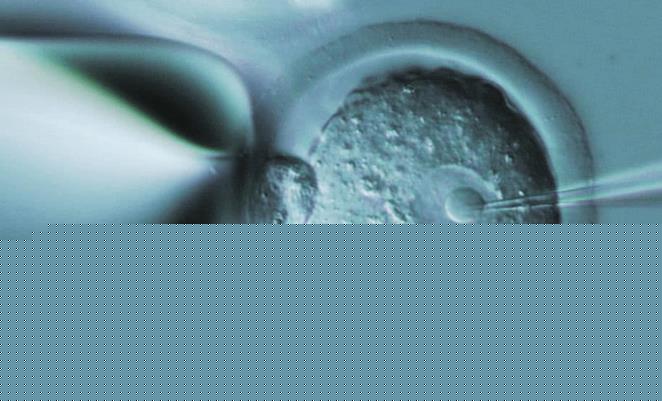

关于试管手术的疑问总是非常多,而且近些年对该手术感到好奇的人也变得更多了,这也意味着生育难题确实更严峻了,也是需要尽快解决的难题,才可以让更多被不孕不育问题折磨的夫妇能够拥有自己的孩子,而试管手术不管是从安全性还是成功率来看,具备的优势都很明显。所以会深受关注以及欢迎,就是自然而然的事情了,那么深圳中山泌尿试管费用大概要多少呢?我们马上来看看具体的情况。

做了试管手术之后,是不是一定会成功呢?面对着这样的问题,就算是水平最高的医院,都不能够给出肯定的答案,其实不论是什么国家的试管机构,都存在着这样子的情况,不过如今的试管手术已经发展到第三代,因此在水平、设备以及手术条件都可以符合要求的情况下,成功率当然也会更高,朋友们保持平常心就好,不需要过于担心。